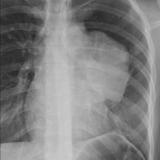

Case 8a Thymoma PA

Date: 03/27/2009

Views: 9539